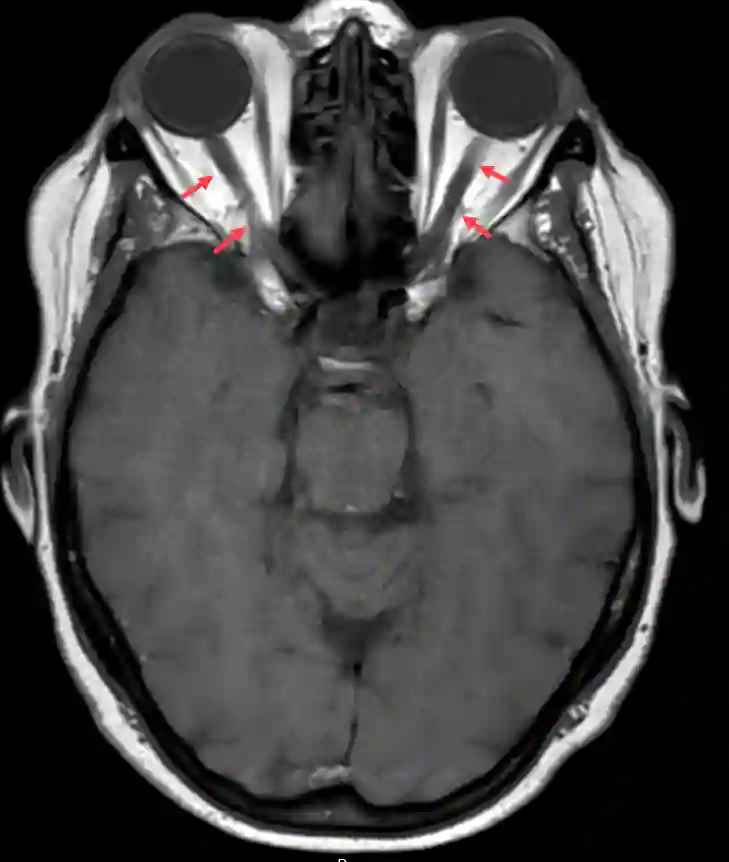

Bildgebung

Der Nervus opticus als auch das Chiasma opticum kann in einer MRT Bildgebung dargestellt werden.

Nervus opticus MRT

Darstellung des Nervus opticus in einer axialen T1 MRI Sequenz.